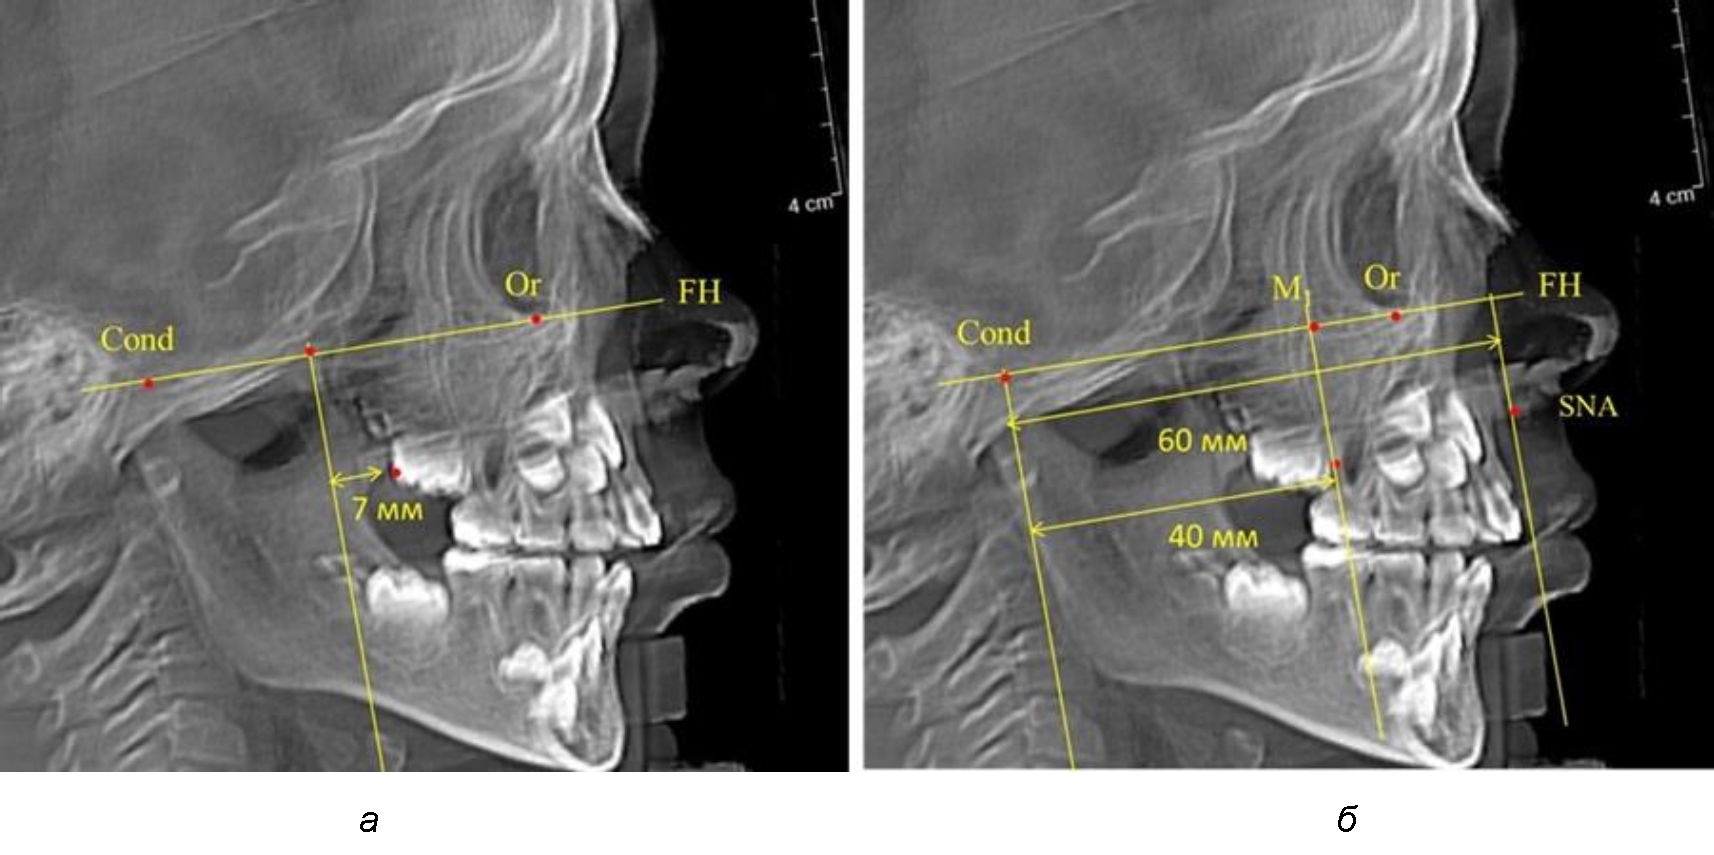

Рис. 4. Особенности положения первых моляров по R. E. McDonald (а) и по предложенному методу (б) у ребенка 4 лет

Второй частью исследования был анализ положения первых постоянных моляров в различные периоды сменного прикуса. На телерентгенограммах детей периода прикуса молочных зубов дистальная поверхность зачатка первого постоянного моляра отстояла от крыловидной вертикали на величину, составляющую около 7 мм, что было близким по значению к данным R. E. McDonald. Сагиттальный размер гантического отдела составлял около 60 мм, а его отношение к кондилярно-молярной глубине – 1,5 (рис. 4).

Рис. 5. Особенности положения первых моляров по R. E. McDonald (а) и по предложенному методу (б) у ребенка 8 лет

По мере роста челюстей увеличивалась глубина гнатического отдела лица, и кондиллярно-спинальный размер составлял в среднем (74,57 ± 0,93) мм. Дистальная поверхность первого постоянного моляра отстояла от крыловидной вертикали на величину, составляющую около 11 мм, что, так же, как и в периоде прикуса молочных зубов, было близким по значению к данным R. E. McDonald, а именно возраст, плюс 3 мм. Однако величина ошибки среднего значения свидетельствовала о вариабельности признака даже в восьмилетнем возрасте после замены передней группы зубов и установки ключевых постоянных моляров в окклюзионное равновесие. Обращает на себя внимание отношение глубины гнатического отдела лица к дистальному отделу, а именно к кондилярно-молярному расстоянию (рис. 5).